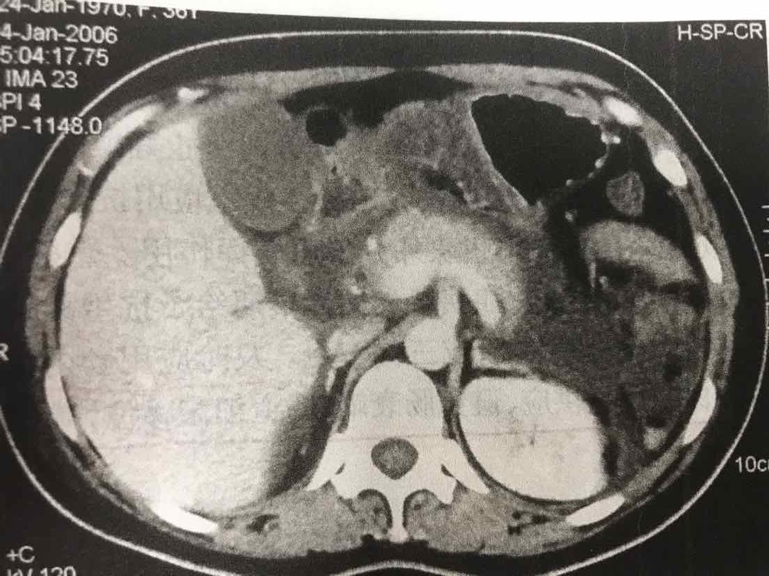

胸腹部增强CT:双侧胸腔积液,双下肺膨胀不全;胰腺周围脂肪密度不均匀增高,胰周及腹腔积液;肝内胆管轻度扩张。

患者Ranson评分>3分(血钙低,白细胞高,血糖高),BalthazarCT分级为E级,考虑为重症胰腺炎。